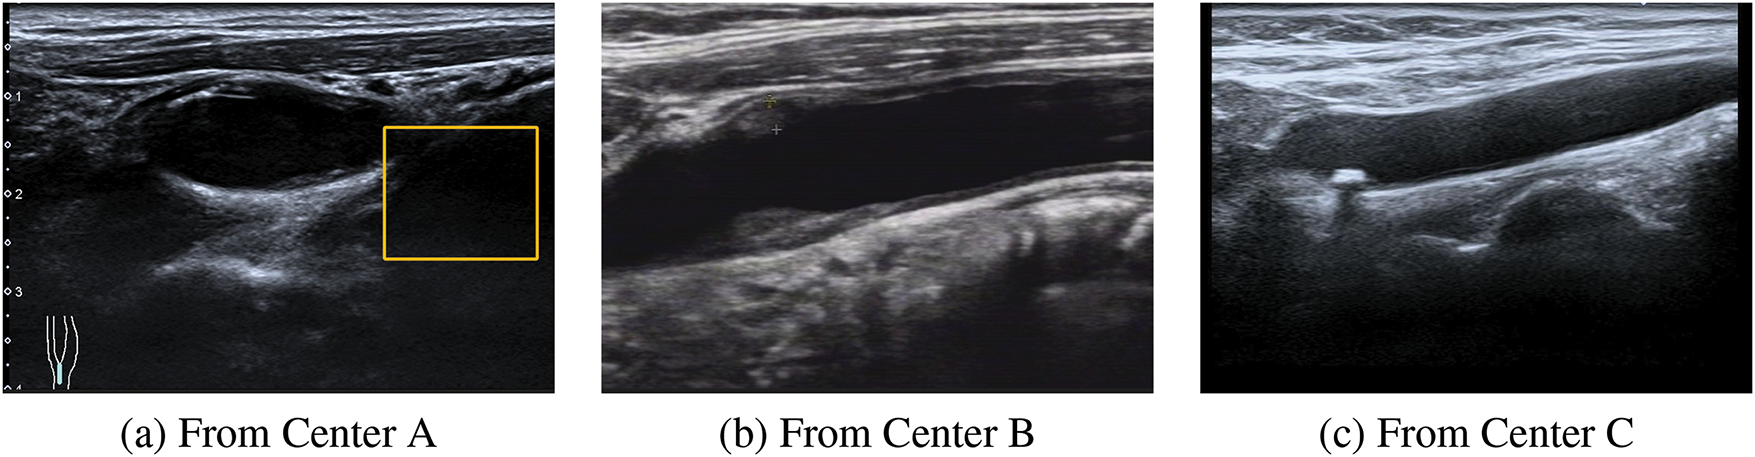

Establishing an appropriate deep learning classification model for multicenter carotid artery plaque ultrasound images still encounters two major challenges: 1) Differences in operators and equipment contribute to variations in ultrasound imaging features, implying substantial disparities in plaque ultrasound data acquired from different centers, resulting in divergent diagnostic outcomes. Consequently, these differences present challenges in unifying unique features within datasets from various centers. 2) Inherent deficiencies in ultrasound imaging, such as low resolution and artifacts, pose significant challenges [10]. Additionally, during examinations, factors like patient swallowing and the operator’s proficiency impact the final image quality of ultrasound [11]. The resulting noise makes it difficult to identify and classify certain data features, leading to the misallocation of erroneous labels by the classifier. Such labels hinder the effective transfer of features across multiple centers. These two difficulties are shown in more detail in Fig. 1. Therefore, it is imperative to address the aforementioned challenges to facilitate seamless integration and accurate analysis within such systems.

Figure 1: An example of the differences in the ultrasound images of plaques from multiple centers. These three images are from three different centers. (1) Plaque ultrasound image noise. (a) The yellow box indicates an ultrasound artifact, which covers part of the useful information and produces noise interference. (b) It is evident that the resolution of this ultrasound image is very low. (2) Feature inconsistency. It can be observed that in (a), (b) and (c) there are obvious differences among the three images, causing certain difficulties for follow-up research